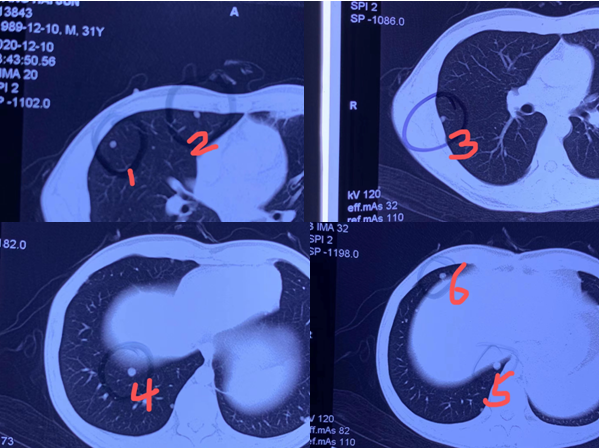

这是一位30岁的年轻女性,两肺3个结节都长大了。刚做完冷冻消融立马问我这次消了几个。我把图片给她看,并告诉她一次消了两肺三个肺结节,本来要两次的手术一次做完了,患者既开心又满意。

▲三个肺结节消融前后对比

消融仅仅针对于肺结节进行杀灭,若患者的身体耐受,且肺功能良好,冷冻消融可以同时一次性处理位于不同肺叶的多个肺结节。曾有一位患者在检查中发现肺结节,在之后的三年体检观察中,又发现有十多个大大小小的磨玻璃样结节,其中有三个结节增大,外院认为一个是原位癌,另外两个是微浸润癌。

病灶

磨玻璃样结节

值得注意的是,这三个病灶分布在双肺,如果都做手术的话,会对患者的身体造成很大的伤害。此外,病灶位于胸膜下,若采取射频消融,容易造成剧烈的疼痛使患者无法耐受。后面患者来到我院就诊。

我在检查时发现,该患者年纪尚轻且肺功能比较良好,没有其他禁忌症,可以尝试冷冻消融,冷冻消融对胸壁的损伤,对患者造成的疼痛都比较低,同时可用两根冷冻针固定病灶,精确冷冻灭活肿瘤。最终,用一次消融为患者解决三个“定时炸弹”。